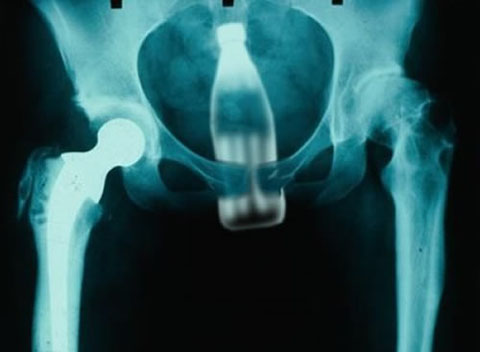

友人の看護師が送信してきたX線画像がテラオソロシイ。

コップ。

救急救命室で働いてた頃、年に10~20人はこの手の患者が来た。

ビンやらスプーンやらなんでもかんでもって感じ。